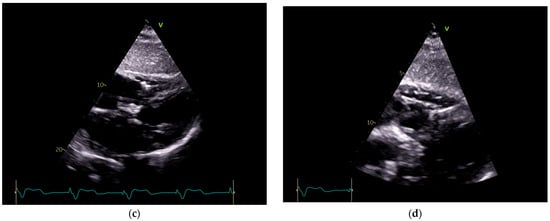

To investigate a potential cause of malfunction of the intracardiac device, it was decided that both a chest X-ray (Figure 2) and an echocardiogram (Figure 3) would be performed. These diagnostic tests were selected to confirm or rule out the possibility of a pacing probe fracture, particularly considering the patient’s recent fall, which may have compromised the integrity of the device or the intracardiac pacing leads. The chest X-ray assesses the device positioning and identifies potential fractures of the pacing leads. Concurrently, the echocardiogram provides critical information regarding cardiac function and its interaction with the implanted device. Together, these diagnostic modalities are essential for optimal management of the patient.

Figure 2.

Patient chest X-ray at admission: a cardiac pacemaker is present in the right pectoral region with a ventricular stimulation lead placed on the free wall of the right ventricle and an abandoned atrial lead. There is no apparent lead displacement or fracture. The inferior segment of the left border of the heart is elongated and bulging. An aortic prosthetic valve is present. There are no pleural or pulmonary lesions.